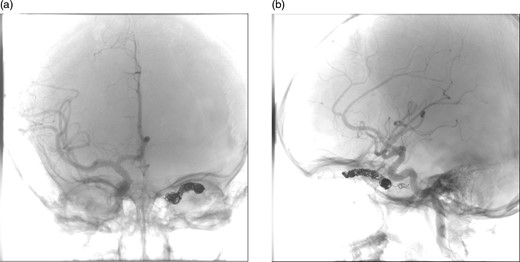

(a) and (b) Post-procedural digital subtraction angiogram under general anaesthesia shows no evidence of a residual CCF following coil embolization.

After a discussion that involved the neuroradiology team, neurosurgical team, the patient and her family, a decision was made to proceed with endovascular treatment of the fistula. Following informed consent from the patient's parents, the procedure was performed under general anaesthesia. Axis to the right common femoral artery was achieved with a 6-French micropuncture kit. A 6-French sheath was inserted into the right common femoral vein. A 6-French guide catheter was placed in the left internal jugular bulb. Thereafter, 4-French sheath was placed in the left common femoral vein. Then, a 4-French Weinberg catheter was placed in the left common carotid. A Headway microcatheter was advanced into the cavernous sinus trough the petrosal sinus into the cavernous sinus and subsequently into the dilated ophthalmic vein. Multiple coils were then placed into the ophthalmic vein throughout its course in the orbit back as far as the anterior section of the cavernous sinus. This resulted in near complete occlusion of the fistula. No immediate complications occurred, and the patient woke without any new neurological deficit in recovery (Fig. 3).